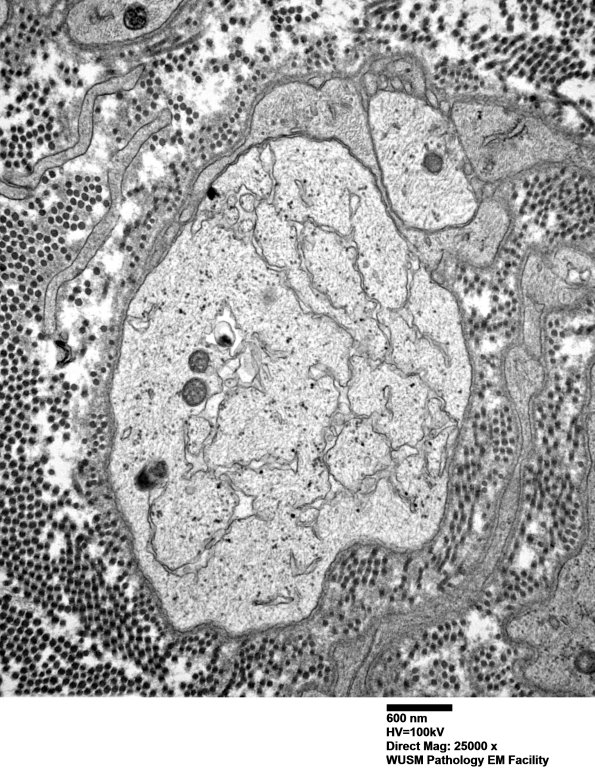

5B4,5 A number of demyelinated axons have an increased intra-axonal proliferation of endoplasmic reticulum-like tubular structures which appear to originate as invaginations of the axolemma. These structures resemble an unusual artifact (see artifacts section) but there is little to suggest crush artifact in this case. (electron micrographs)